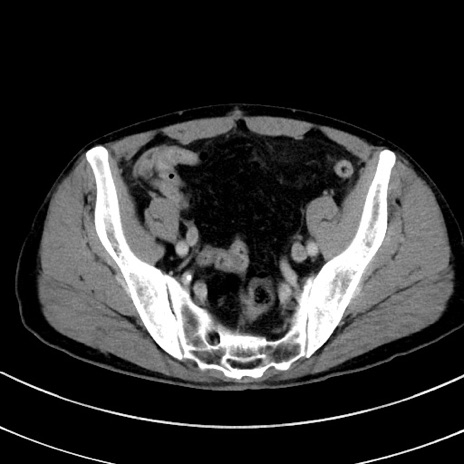

症例8(横断像)

【症例】 60歳代男性

【主訴】 黒色吐物

【現病歴】 4日前から嘔気自覚、2日前の朝食後にも嘔気あり、自分で手で嘔吐反射起こし嘔吐したところ血が混ざっていたため受診。

【既往歴】 5年前汎発性腹膜炎を伴う急性虫垂炎で手術、高血圧、前立腺肥大症、高脂血症

【身体所見】 腹部正中に手術癩痕あり 腹部平坦・軟圧痛なし膨満感あり

【データ】WBC 8400、CRP 4.54